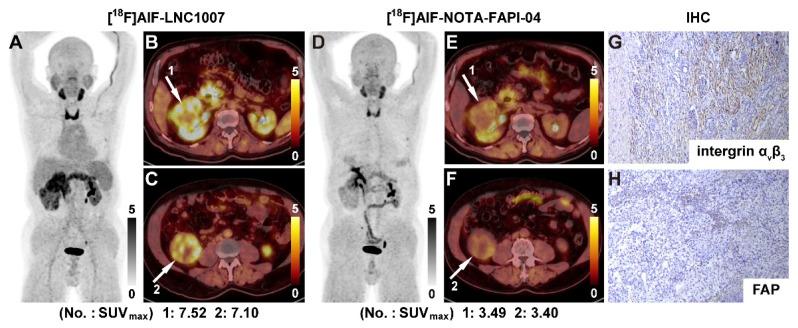

Renal cell carcinoma (RCC) is a significant global health concern, and the early diagnosis and accurate staging of clear cell renal cell carcinoma (ccRCC) remain major challenges. [F]FDG PET/CT is not ideal for diagnosing ccRCC due to the low glucose metabolism potential of cancer cells. Both fibroblast activation protein (FAP) and the angiogenic integrin αβ receptor are closely linked to the pathogenesis and progression of ccRCC. The aim of this study is to evaluate a novel radiopharmaceutical [F]AlF-NOTA-FAPI-RGD (denoted as [F]AlF-LNC1007), a dual-targeting heterodimer tracer targeting both FAP and integrin αβ, and to compare the diagnostic value of [F]AlF-LNC1007 with [F]FDG and [F]AlF-NOTA-FAPI-04 PET/CT in RCC. : A total of 35 participants, highly suspected to have RCC, were recruited. [F]AlF-LNC1007 and [F]AlF-NOTA-FAPI-04/[F]FDG scans were performed at least one day apart, and both were completed within one week. The Wilcoxon signed-rank test or paired t-test was used to assess differences in tumor uptake and TBR (tumor-to-background ratio) between [F]AlF-LNC1007 and the other two imaging agents. The Spearman correlation coefficient was used to evaluate the correlation between tumor uptake and the expression of FAP and αβ The detection rate, sensitivity, and positive predictive value (PPV) of [F]AlF-LNC1007 for RCC primary lesions were significantly higher than those of [F]FDG, at 91% vs. 76%, 100% vs. 85%, and 91% vs. 87%, respectively. Obvious advantages were also seen in metastatic lesions at 94% vs. 34%, 94% vs. 29%, and 100% vs. 100%. Compared to [F]AlF-NOTA-FAPI-04, the corresponding detection rate, sensitivity, and PPV were 98% vs. 90%, 100% vs. 92%, and 98% vs. 98% for primary lesions, and 89% vs. 78%, 89% vs. 93%, and 100% vs. 82% for metastatic lesions. The uptake and TBR of [F]AlF-LNC1007 in both primary and metastatic lesions were significantly higher than those of [F]FDG (all P < 0.001). The uptake of [F]AlF-LNC1007 showed a moderate to high positive correlation with the expression levels of αβ and the combined expression of FAP and αβ (r = 0.756, P = 0.0003; r = 0.678, P = 0.0002) and a low positive correlation with FAP expression alone (r = 0.389, P = 0.014). The uptake of [F]AlF-NOTA-FAPI-04 showed a low to moderate positive correlation with FAP expression and the combined expression of FAP and αβ (r = 0.570, P = 0.0002; r = 0.408, P = 0.010), and no correlation with αβ expression alone (r = 0.262, P = 0.107). [F]AlF-LNC1007 demonstrated significantly higher diagnostic efficacies and uptake in primary and metastatic renal cell carcinoma (RCC) compared to FDG PET/CT. Additionally, [F]AlF-LNC1007 exhibited higher diagnostic efficacies and uptake in primary RCC than [F]AlF-NOTA-FAPI-04 PET/CT. While these findings suggest potential diagnostic advantages, further studies are needed to fully evaluate its diagnostic efficacy compared to the standard of treatment.